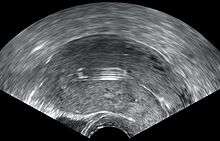

- A "lost coil" occurs when the thread cannot be felt by a woman on routine checking and is not seen on speculum examination.[42] Various thread collector devices or simple forceps may then be used to try to grasp the device through the cervix.[43] In the rare cases when this is unsuccessful, an ultrasound scan may be arranged to check the position of the coil and exclude its perforation through into the abdominal cavity or its unrecognised previous expulsion.